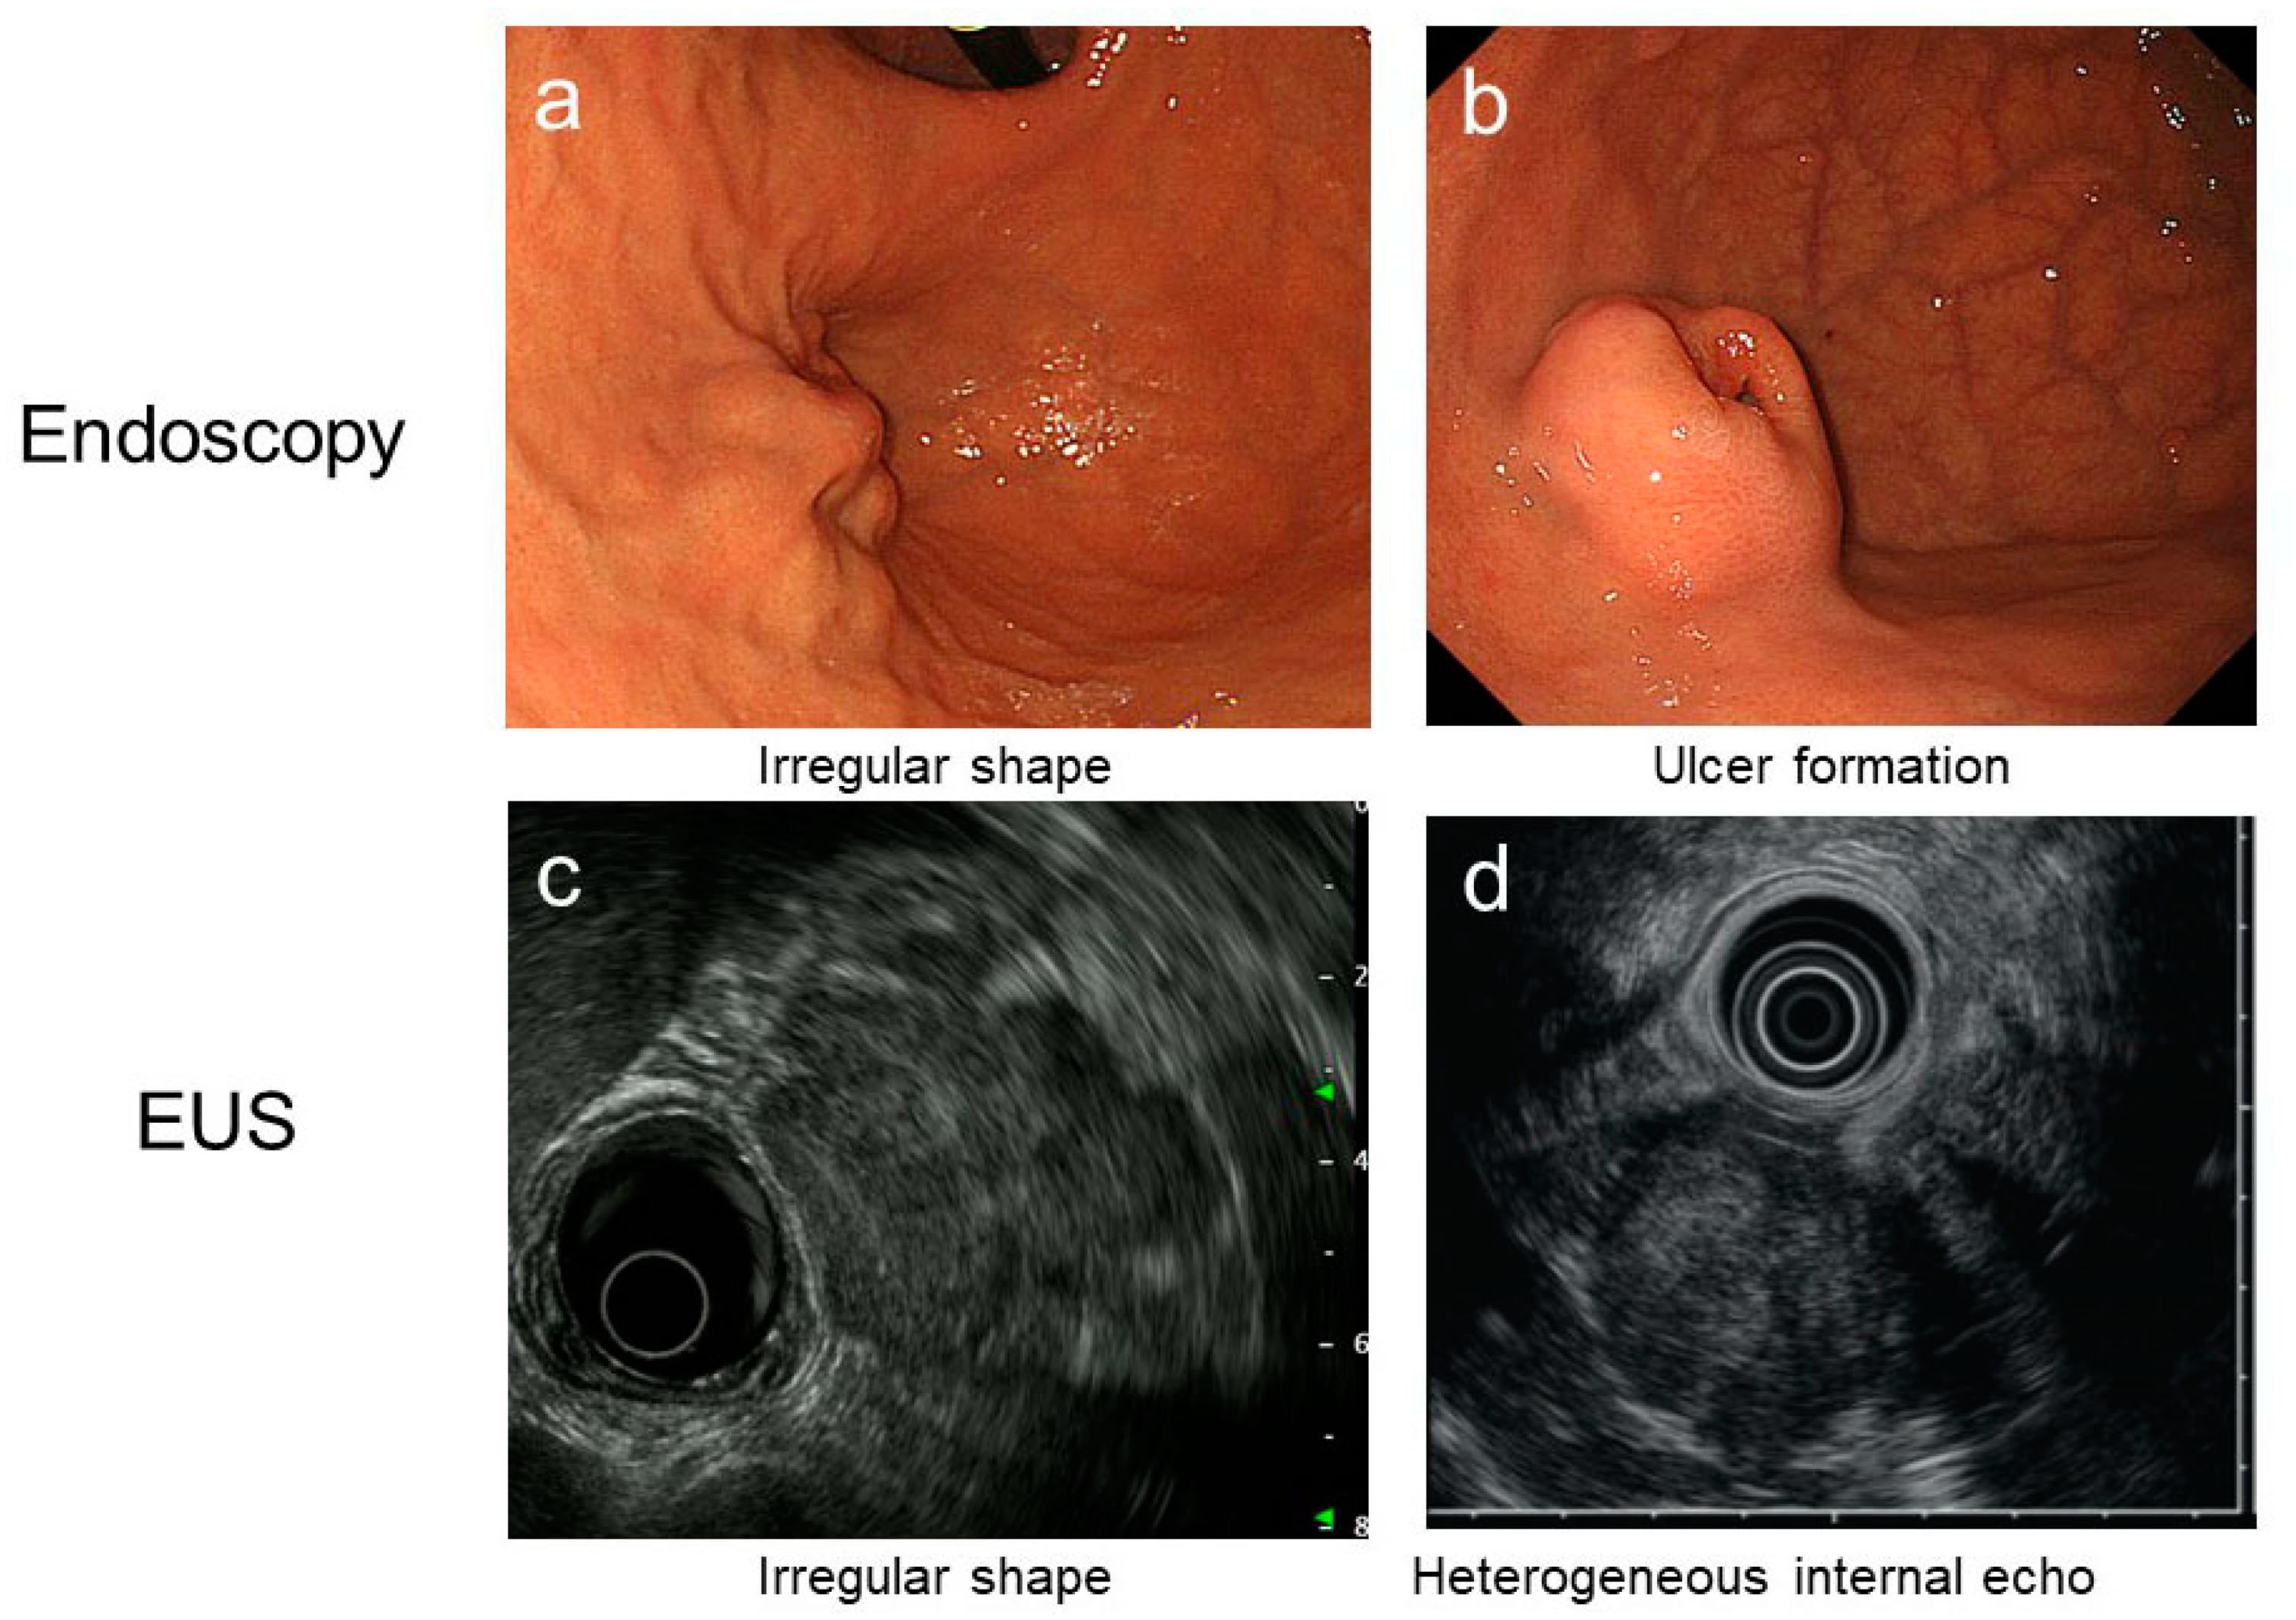

| Disease | Endoscopic Findings | EUS Findings | Pathological Features | |||

|---|---|---|---|---|---|---|

| Surface, Form, etc. | Major Location | Main Layer | Echo Findings | Morphology | IHC; Genetic Changes | |

| GIST | hemi-spherical, occasionally with delle or ulcer | body | proper muscle, rarely submucosa | hypoechoic, heterogenous with increased malinancy | spindle cell > epithelioid cell | KIT, DOG1; mutation in KIT or PDGFRA |

| Myogenic tumor & Leiomyoma | hemi-spherical, intact mucosa | near cardia | proper muscle, sometimes submucosa | round, hypoechoic, homogenous | spindle cell (eosinophilic cell) | Desmin, α-SMA |

| Schwanomma & neurogenic tumor | hemi-spherical, intact mucosa | body, lesser curvature | proper muscle, sometimes submucosa~deep mucosa | hypoechoic, homogenous~slightly heterogeneous | spindle cell, palisading, Verocay body, lymphoid cuff in Schwannoma | S-100, SOX10, NSE in neurogenic tumor |